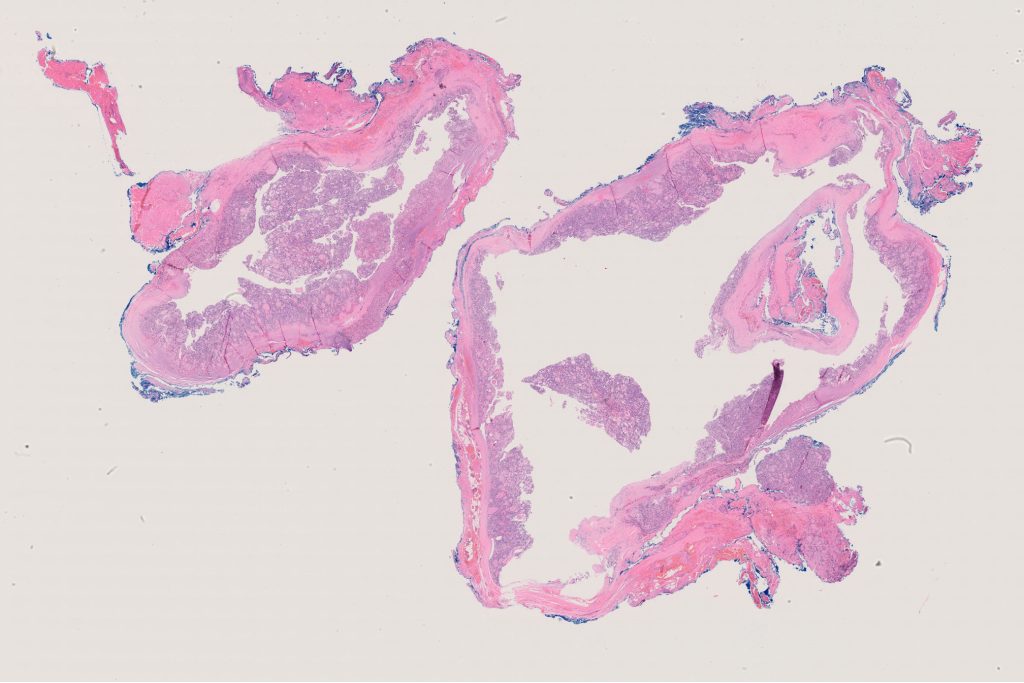

TSK 002.1.ndpi

129024

x

86016

@

40X